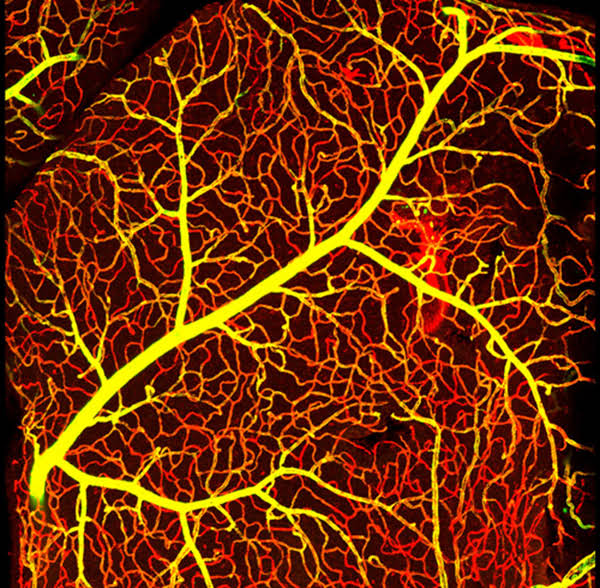

為促進科學(xué)文化發(fā)展,活躍專委會的科技人文氛圍,培養(yǎng)科研工作者的創(chuàng)新意識,激發(fā)他們發(fā)現(xiàn)美、創(chuàng)造美的熱情和興趣,本次年會特別增加了一項“生命的藝術(shù)——首屆年度顯微圖片展”活動。在專委會發(fā)出征稿通知之后,來自全國近20 所院校的師生積極響應(yīng),共投稿顯微攝影作品125 幅。經(jīng)以王松靈院士為主席的九位審讀專家組成員在線上線下的認真審閱和討論,從圖片的原創(chuàng)性、科學(xué)性和藝術(shù)性三個方面進行綜合考量,最終確定年度圖片1 幅,年度提名圖片20 幅。在此匯集成冊,與各位同仁分享、交流。

這些作品幾乎均為創(chuàng)作者在日??蒲泄ぷ髦幸圆煌募夹g(shù)手段捕捉到的微觀生命瞬間,科學(xué)的“透鏡”似乎為我們展現(xiàn)出一幅幅藝術(shù)的“魔幻”,一邊是細胞、分子層面的微觀抵達,另一邊好似一塊既陌生又熟悉的“優(yōu)詩美地”。這里,本是科學(xué)嚴謹?shù)念I(lǐng)地,因為其關(guān)乎生靈,便開啟人們自由逸放的審美思緒。在此,我們驚嘆中國古代哲學(xué)體系中“天人合一、道法自然”的天道規(guī)律。原來早于現(xiàn)代科學(xué),這種“盡精微而致廣大”的宇宙觀便已根植于我們生存的大地。感謝各位作者以他們現(xiàn)代技術(shù)的視野,為我們定格生命律動的瞬間,張揚蓬勃的藝術(shù)活力。換一個視角,生命的風景便呈現(xiàn)“天地人”的和諧和統(tǒng)一,換一種思路,生命的哲學(xué)便更能詮釋苦難與幸福的非凡境遇。